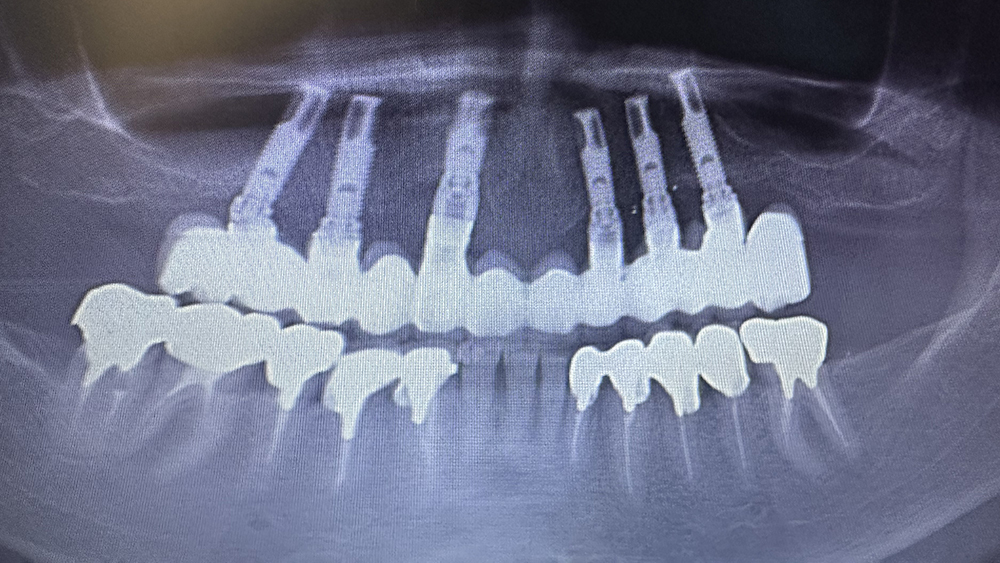

症例4

Before

After

KYさん、50代男性

治療の期間・回数:約6か月

​治療の価格:約3,300,000円

治療内容:この方は40代で歯がほとんどなく、12年前に上あごに6本、下あごに4本のインプラントを使って、手術当日に仮の歯を入れる「即時荷重」で治療しました。

上の歯は当初、安価な金属のフレームに入れ歯の歯を並べたものを装着しました。

しかし、強い歯ぎしりのため、上の歯は3年で壊れ、修理して再装着しても2年でまた壊れてしまいました。そこで、丈夫なコバルトクロムのフレームにフルジルコニアの歯を接着した最高強度のブリッジに作り替え、見た目を良くするため人工の歯ぐきを付けました。

このブリッジは高価な技工物ですが、約80万円の原価で製作しました。

再装着してから7年経ちますが、今のところ問題なく安定しています。